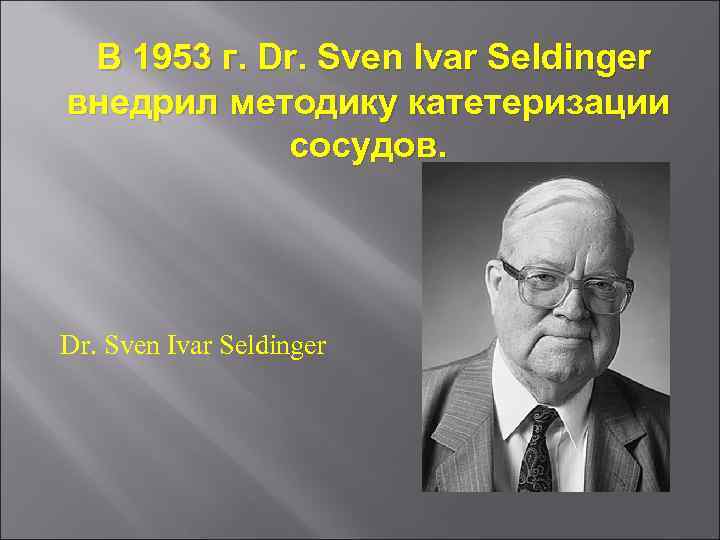

В 1953 г. Dr. Sven Ivar Seldinger внедрил методику катетеризации сосудов. Dr. Sven Ivar Seldinger

В 1953 г. Dr. Sven Ivar Seldinger внедрил методику катетеризации сосудов. Dr. Sven Ivar Seldinger